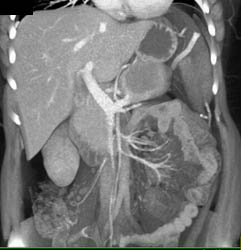

Pancreatic Cancer Arises in Chronic Pancreatitis With Superior Mesenteric Vein (SMV) Encased